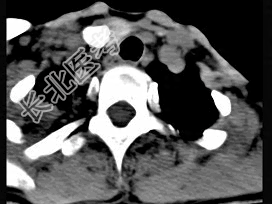

- 多项选择题50岁女性患者,体检发现右侧甲状腺有较硬结节, CT扫描如图所示,请选择正确的描述和答案 ( )

A、右侧甲状腺内见稍低密度影,周边围以环形致密钙化影

B、肿块影与周围结构分界清楚

C、考虑为结节性甲状腺肿

D、考虑为甲状腺癌

E、考虑为甲状腺腺瘤钙化